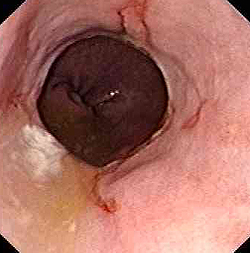

Эзофагоскопия при химическом ожоге пищевода

Стриктура пищевода после химического ожога

в) Диагностика. Диагноз устанавливают на основании типичного анамнеза (случайное или преднамеренное (с целью суицида) употребление едкого вещества) и характерных местных признаков. Следует выяснить природу едкого вещества, выполнить рентгенографию грудной клетки и живота. Если по данным анамнеза и клинического обследования ожог не тяжелый, то выполняют контрастное рентгенологическое исследование пищевода, после чего осторожно исследуют пищевод и желудок эндоскопом и вводят желудочный зонд.

Противопоказаниями к эзофагоскопии и зондированию желудка являются шок и подозрение на перфорацию. Эзофагоскопию сразу при поступлении больного можно выполнить лишь в том случае, если протяженность и глубину ожога пищевода оценить невозможно.

Первую эзофагоскопию с соблюдением необходимых предосторожностей выполняют через 6-8 дней. Если при рентгенологическом исследовании и эзофагоскопии выявляют стеноз пищевода, то с конца 2-й недели начинают дилатацию пищевода. В дальнейшем эзофагоскопию выполняют каждые 10 дней, пока дефекты слизистой оболочки не эпителизируют. После этого контрольную рентгенографию и эзофагоскопию выполняют через 1, 3, 6 и 12 мес.

После стабилизации общего состояния возможно проведение рентгенографии пищевода. В острой фазе ожога на рентгенограмме отмечается утолщение складок слизистой оболочки, данные за гиперкинезию пищевода. Консультация врача-эндоскописта в остром периоде более информативна: во время эзофагогастроскопии визуализируется гиперемия и отек эпителия, изъязвления и эрозии пищевода, налеты. В подострой фазе рентгенография пищевода выявляет стриктуры, расширение пищевода над стенозированным участком, умеренный эзофагит. Эндоскопическое исследование в подостром периоде позволяет обнаружить некротический струп, определить границы поражения, визуализировать грануляции и формирующиеся рубцы. В хронической стадии процесса можно выявить разнообразные виды рубцовых изменений: клапанные, в виде колец, трубчатые и др. Изредка рубцы пищевода могут малигнизироваться.